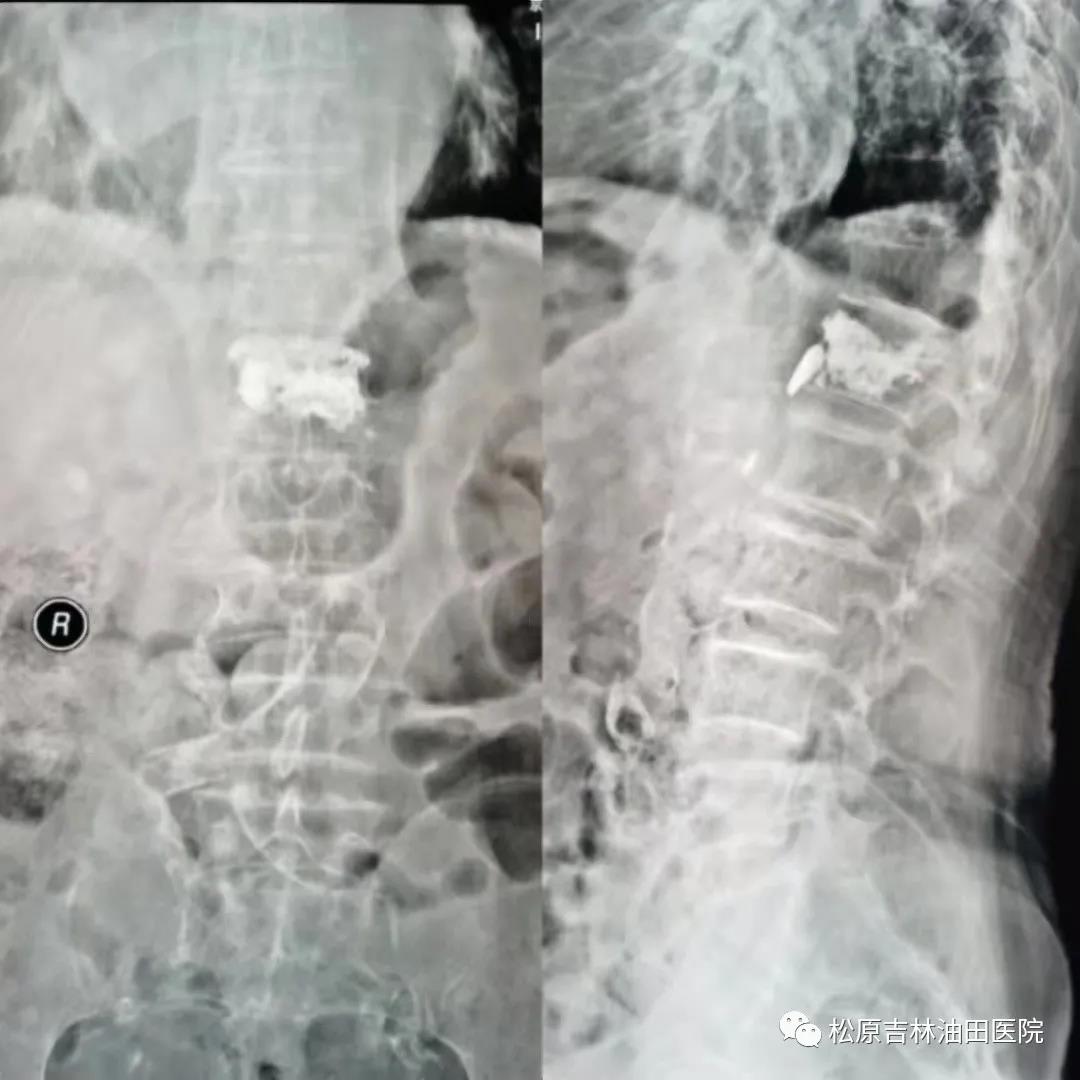

同一天手术的还有病人**苹,患者有明显的脊柱侧弯及旋转,脊柱拧得跟“麻花”一样,定位和穿刺难度可想而知,在王大伟主任,许德慧副主任,邹双伟主任医师,包刚副主任医师,殷国超主治医师及范加俊医师的共同努力下,C形臂被摆出了各种各样奇怪的姿势,最终确保了定位准确和手术的成功。

患者**苹 术后影像(骨水泥得到良好弥散、填充、支撑)与术前影像对比